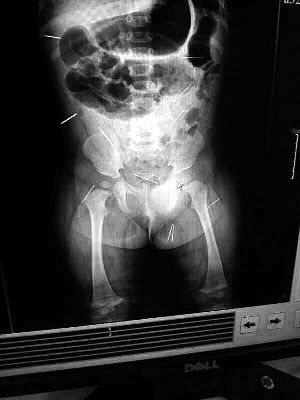

山東聊城11個月女嬰萱萱(化名)疑似被人以12根鋼針插滿臀部、腹腔等部位,昨天在兒童醫(yī)院會診后,醫(yī)生稱3根針靠近胸腔最危險,首批先行取出,預(yù)計將在下周二手術(shù)。孩子父母稱孩子一直由家人照顧,自家與他人并無冤怨。山東警方表示正在偵破中,不便透露案情。

“要不是當初那幾個紅點,可能到現(xiàn)在我們還不知道孩子身體里有鋼針!”昨天,在兒童醫(yī)院住院處,萱萱爸爸范先生稱,日前原本很愛笑的萱萱突然變得有些焦躁,一抱起來就哭,孩子母親偶然間在萱萱屁股上發(fā)現(xiàn)了幾個小紅點兒,原以為是蚊蟲叮咬,就醫(yī)結(jié)果卻讓人不寒而栗?!搬t(yī)院拍出的片子上,萱萱的體內(nèi)有12根鋼針,插滿臀部、腹腔、骨盆等各個部位?!狈断壬榻B,因為鋼針已深入體內(nèi),要是孩子不哭鬧,他們很難發(fā)現(xiàn)。

北京晨報記者了解到,目前體內(nèi)的12根鋼針多分布在孩子的臀部,一根在腹部,其余3根在胸腔附近,其中一根很接近心臟?!耙驗楹⒆犹?,醫(yī)生們害怕取針的時候?qū)λ斐蓚Γ谛厍桓浇?針可能會威脅她的生命”。